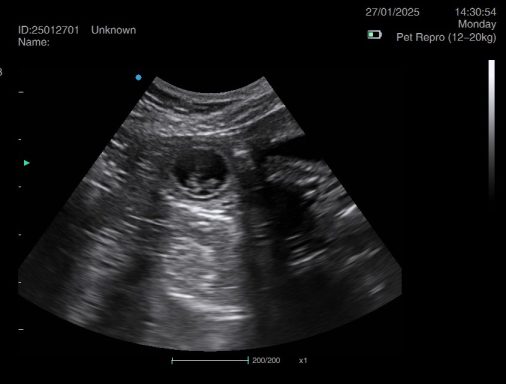

Ultrasound pregnancy scanning is a safe, non-invasive way to confirm pregnancy in dogs and cats, offering breeders and pet owners peace of mind and vital information to support responsible care. It allows us to detect gestational sacs, assess foetal development, and estimate litter size—all while ensuring the wellbeing of the animal.

Pregnancy can sometimes be detected as early as Day 18 post-mating, but scanning at this stage is not routinely recommended. Embryos are still developing and may not be clearly visible, and there is a natural risk of embryo resorption, which can lead to misleading or inconclusive results.

For the most accurate and reliable scan, we advise booking between Day 25 and Day 32, when pregnancy is more easily confirmed and foetal structures are clearer. If an early scan is performed and no pregnancy is detected, we offer a FREE complimentary re-scan after 7 days at the clinic to ensure clarity and support informed decision-making.

Our approach balances early insight with ethical care—always prioritizing the comfort of the animal and the accuracy of the results.

Gallery